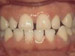

Crowding of the teeth